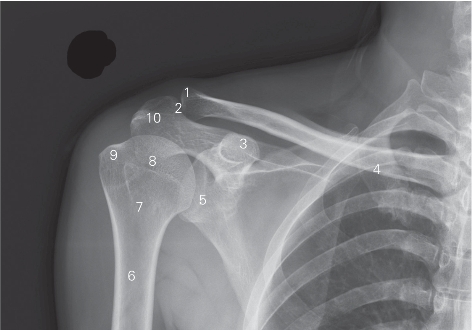

图7-1 肩关节正位DR平片

1 肩峰端 acromial end 2 肩锁关节 acromioclavicular joint

3 喙突 coracoid process 4 锁骨 clavicle

5 关节盂 glenoid cavity 6 肱骨 humerus

7 外科颈 surgical neck 8 解剖颈 anatomical neck

9 大结节 greater tubercle 10 肩峰 acromion